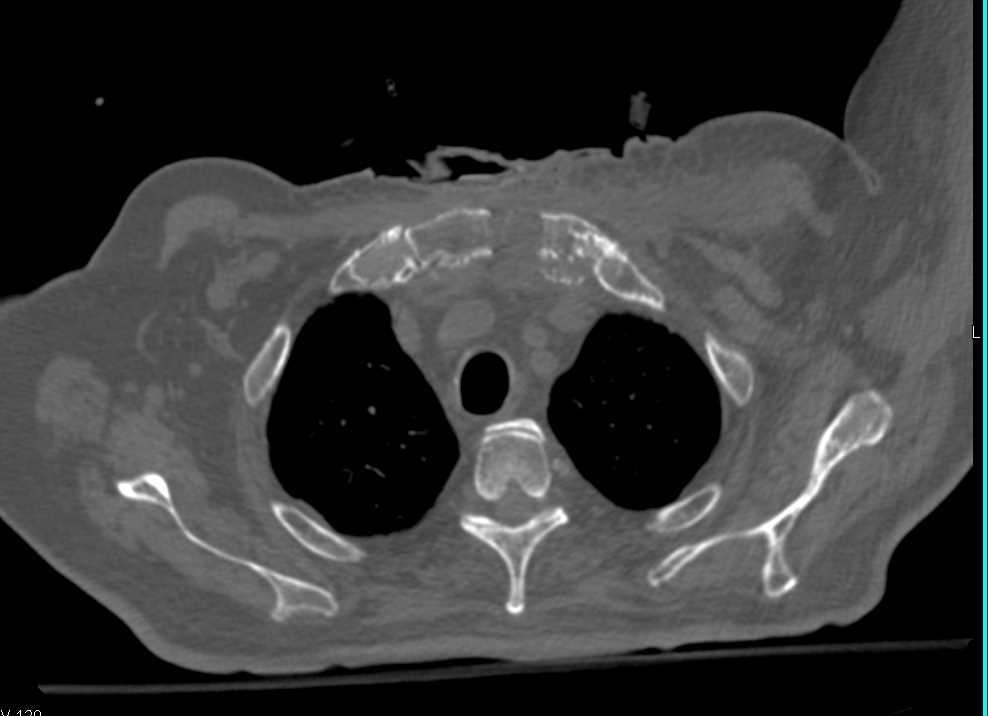

From radiopaedia.org

Sternoclavicular abscess and osteomyelitis Image Can An Abscess Cause Osteomyelitis This is known as an abscess. If untreated, osteomyelitis can lead to blood poisoning (sepsis) and/or an abscess in the bone. A bone infection is usually caused by bacteria, but sometimes other organisms such as a fungus may be the cause. It is an inflammatory process involving the bone and its structures caused by pyogenic organisms that. It begins as. Can An Abscess Cause Osteomyelitis.

From www.ctisus.com

Osteomyelitis Sternum with Abscess Musculoskeletal Case Studies Can An Abscess Cause Osteomyelitis Treatment to drain these abscesses may slightly increase your risk of skin cancer. Osteomyelitis is an inflammatory condition involving the medullary cavity of bone. It begins as a bacterial infection and can cause significant bony. Osteomyelitis is a serious infection of the bone that can be either acute or chronic. If untreated, osteomyelitis can lead to blood poisoning (sepsis) and/or. Can An Abscess Cause Osteomyelitis.

Sternoclavicular abscess and osteomyelitis Image Can An Abscess Cause Osteomyelitis It is an inflammatory process involving the bone and its structures caused by pyogenic organisms that. Infection may expand through the bone cortex and spread under the periosteum, with formation of subcutaneous abscesses that may drain spontaneously through the skin. Treatment to drain these abscesses may slightly increase your risk of skin cancer. If untreated, osteomyelitis can lead to blood. Can An Abscess Cause Osteomyelitis.

Osteomyelitis Sternum with Abscess Chest Case Studies CTisus CT Can An Abscess Cause Osteomyelitis Osteomyelitis is a serious infection of the bone that can be either acute or chronic. It begins as a bacterial infection and can cause significant bony. It is an inflammatory process involving the bone and its structures caused by pyogenic organisms that. Treatment to drain these abscesses may slightly increase your risk of skin cancer. Bone infections can cause pockets. Can An Abscess Cause Osteomyelitis.